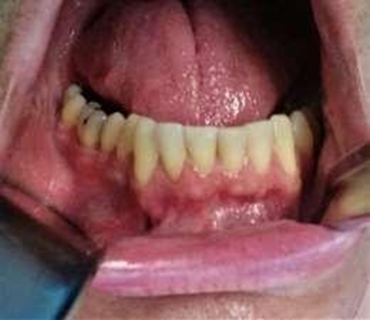

Figure 1. Intra and extra oral

clinical appearance.

infection. (Figure 4). Shows the

results obtained after 4 weeks of decompression. A notable reduction in

vestibular mass can be visualized in this image and the patient reported a

major pain relief. Future cyst enucleation was decided according to radiologic

evaluation of the cystic size and affected bone.

Figure 4. Cystic decompression result after 4 weeks.